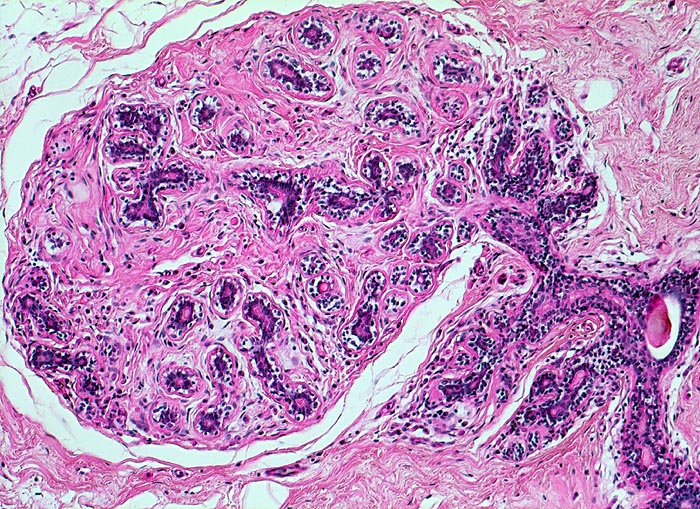

Makroskopisch bildet das mastopathisch veränderte Parenchym weisse kompakte fibröse Areale mit Einschluss von Zysten, welche oftmals eingedicktes Sekret enthalten. Neben einer Stromafibrose und zystisch ausgeweiteten Gängen mit Sekretretention findet sich oft eine unterschiedlich ausgeprägte intraduktale Proliferation von luminalen und basalen Epithelzellen. Nicht selten liegen als Begleitbefund kleine Fibroadenome, eine sklerosierende Adenose oder Gänge mit apokriner Metaplasie vor. Oftmals finden sich auch intraduktale Mikroverkalkungen. Die duktale Hyperplasie ist im Gegensatz zur atypischen Hyperplasie und zum Carcinoma in situ charakterisiert durch eine bunte, ungeordnete Proliferation ungleich grosser polygonaler bis spindeliger Zellen mit Ausbildung von schlitzförmigen Hohlräumen oder dünnen epithelialen Brücken. Die euchromatischen Kerne variieren in Grösse, Form und Lagerung. Bei paralleler Lagerung der Kerne entsteht der Eindruck eines Strömens und Fliessens der Zellen. Das duktale Carcinoma in situ ist von gutartigen intraduktalen Epithelproliferationen abzugrenzen aufgrund seiner Monomorphie (> 5185), Hyperchromasie der Zellkerne und starrer geometrischer Muster (runde scharf begrenzte wie ausgestanzte Lumina (> 5184), breite Brücken und Bögen, Mikropapillen). Eine intraduktale Epithelproliferation mit Atypie wird dann diagnostiziert, wenn nur ein Teil der Gänge oder Läppchen die typischen Veränderungen eines Carcinoma in situ zeigt. Die Abgrenzung der atypischen Hyperplasie von der Hyperplasie ohne Atypie erfolgt aufgrund qualitativer Merkmale und die Abgrenzung der Hyperplasie mit Atypie vom Carcinoma in situ aufgrund quantitativer Merkmale.

• Ausgeprägte Fibrose und zystisch erweiterte Gangstrukturen in organoider Anordnung.

• In der Mitte rechts einige Gänge mit gewöhnlicher intraduktaler Epithelhyperplasie ohne Atypie: Polymorphe, sich überlagernde spindelige Zellen. Fliessende Anordnung der Zellen. Schlitzförmige und irregulär geformte Lumina.

• Alle Drüsen zeigen eine erhaltene äussere abgeflachte Myoepithelschicht mit hellem Zytoplasma.